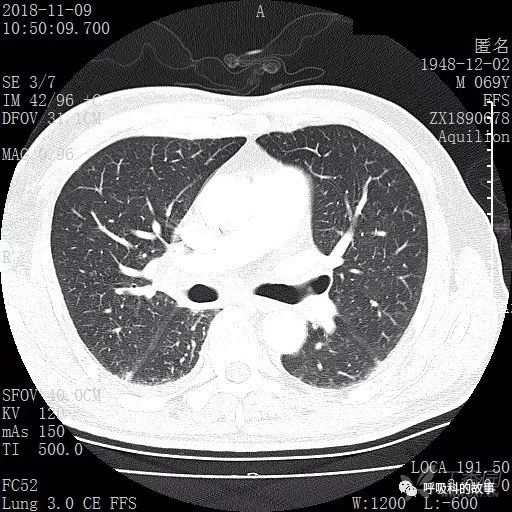

肺窗CT